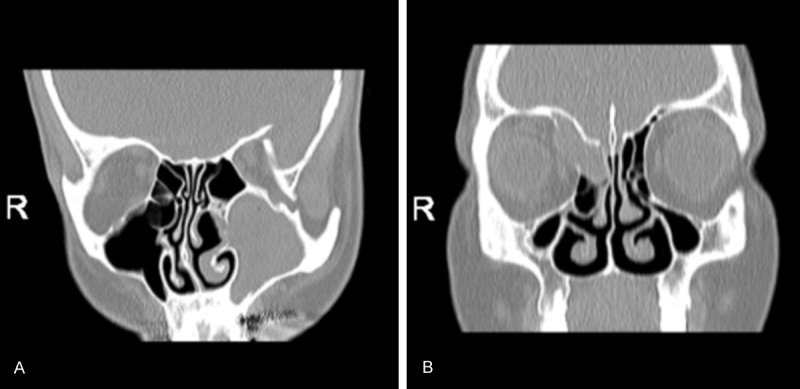

• Các tiêu chuẩn trên CT scan của u nhầy mũi xoang:

• Khối mật độ đồng nhất dạng nang, có bờ rõ, không bắt thuốc cản quang

• Xâm lấn rộng

• Ăn mòn mô xương xung quanh

• Xơ hoá rìa

Hỉnh ảnh u nhầy xoang hàm và xoang sàng trên CT scan (Nguồn: Murat Topdag ,  Mete Iseri ,  Fatih Sari ,  Selvet Erdogan , và I Gurkan Keskin .Paranasal sinus mucoceles: our clinical experiments 2015)